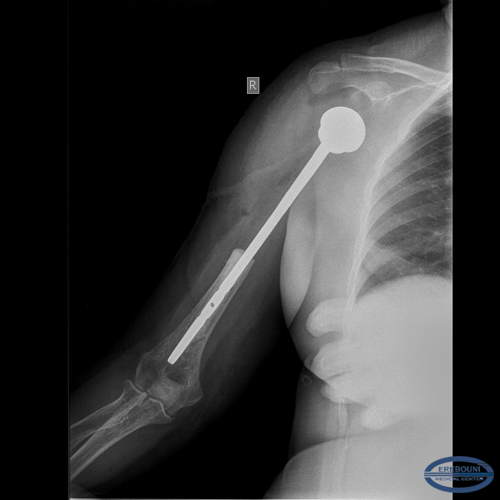

Հիվանդ Ս., 52 տ., 08.12.15թ. ընդունվել էբժշկական կենտրոն գանգատվելով աջ ուսային գոտու շրջանի ցավերից և նշված հոդում շարժումների խիստ սահմանափակումից: Անամնեզ` 5 տարի: Բազմաթիվ անգամ դիմել է բժիշկներին, սակայն համապատասխան հետազոտություն չի անցկացվել: Համալիր հետազոտման արդյունքում հիվանդի մոտ ախտորոշվել է` աջ բազկոսկրի պրոքսիմալ հատվածի խոնդրոսարկոմա:

Ըստ ԿՏ-հետազոտության, հայտնաբերվել է ներոսկրային ուռուցքային ախտահարում 15 սմ երկարությամբ: Ուսագոտու մկանների ներգրավվածություն պրոցեսի մեջ չէր հայտնաբերվել:

08.12.15թ.բժշկական կենտրոնի առաջատար մասնագետ` ուռուցքաբան-վնասվածքաբան, բ.գ.թ. Սարգիս Նազարի Մարգարյանի ղեկավարությամբ, ընդհանուր անզգայացման տակ, կատարվել է բազկոսկրի պրոքսիմալ 2/3 սեգմենտար ռեզեկցիա էնդոպրոթեզավորումով: Մկանային կարկասի ինտակտ լինելը թույլ տվեց լիովին վերականգնել նրանց անատոմիան, հատկապես ենթաթիակային մկանը, որն ունի մեծ դեր ուսային հոդի ֆունկցիայի և կայունության մեջ:

Մակրոպրեպարատի հիստոլոգիական եզրակացությունը`Հասարակ խոնդրոսարկոմա (grade I). Վիրահատական ռադիկալիտետը լիարժեք է (R0):